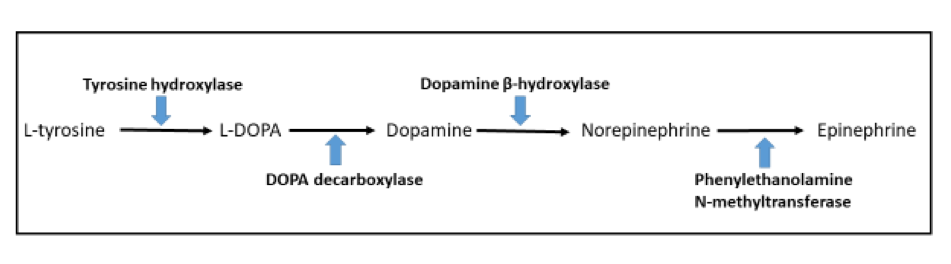

- Dopamine beta hydroxylase and phenylethanolamine N methyltransferase (PNMT) (epinephrine producing tumors) (see Diagram below) (Neuroendocrinology 2015;101:289, J Clin Med 2018;7:280)